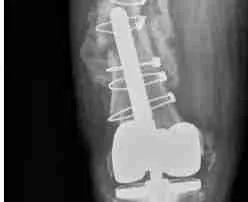

ROSA is a robotic platform that takes a personalized approach to planning for your knee replacement using a three-dimensional model created from special x-rays. These x-rays are matched to your knees to help deliver a personalized knee replacement. Your new knee done with robotic assistance allows for accurate placement of implants with less soft-tissue dissection. Less soft-tissue dissection helps you with quicker recovery and return to your active lifestyle.

Knee Arthroplasty – Partial versus Total

What is a knee arthroplasty? Knee arthroplasty is an [...]